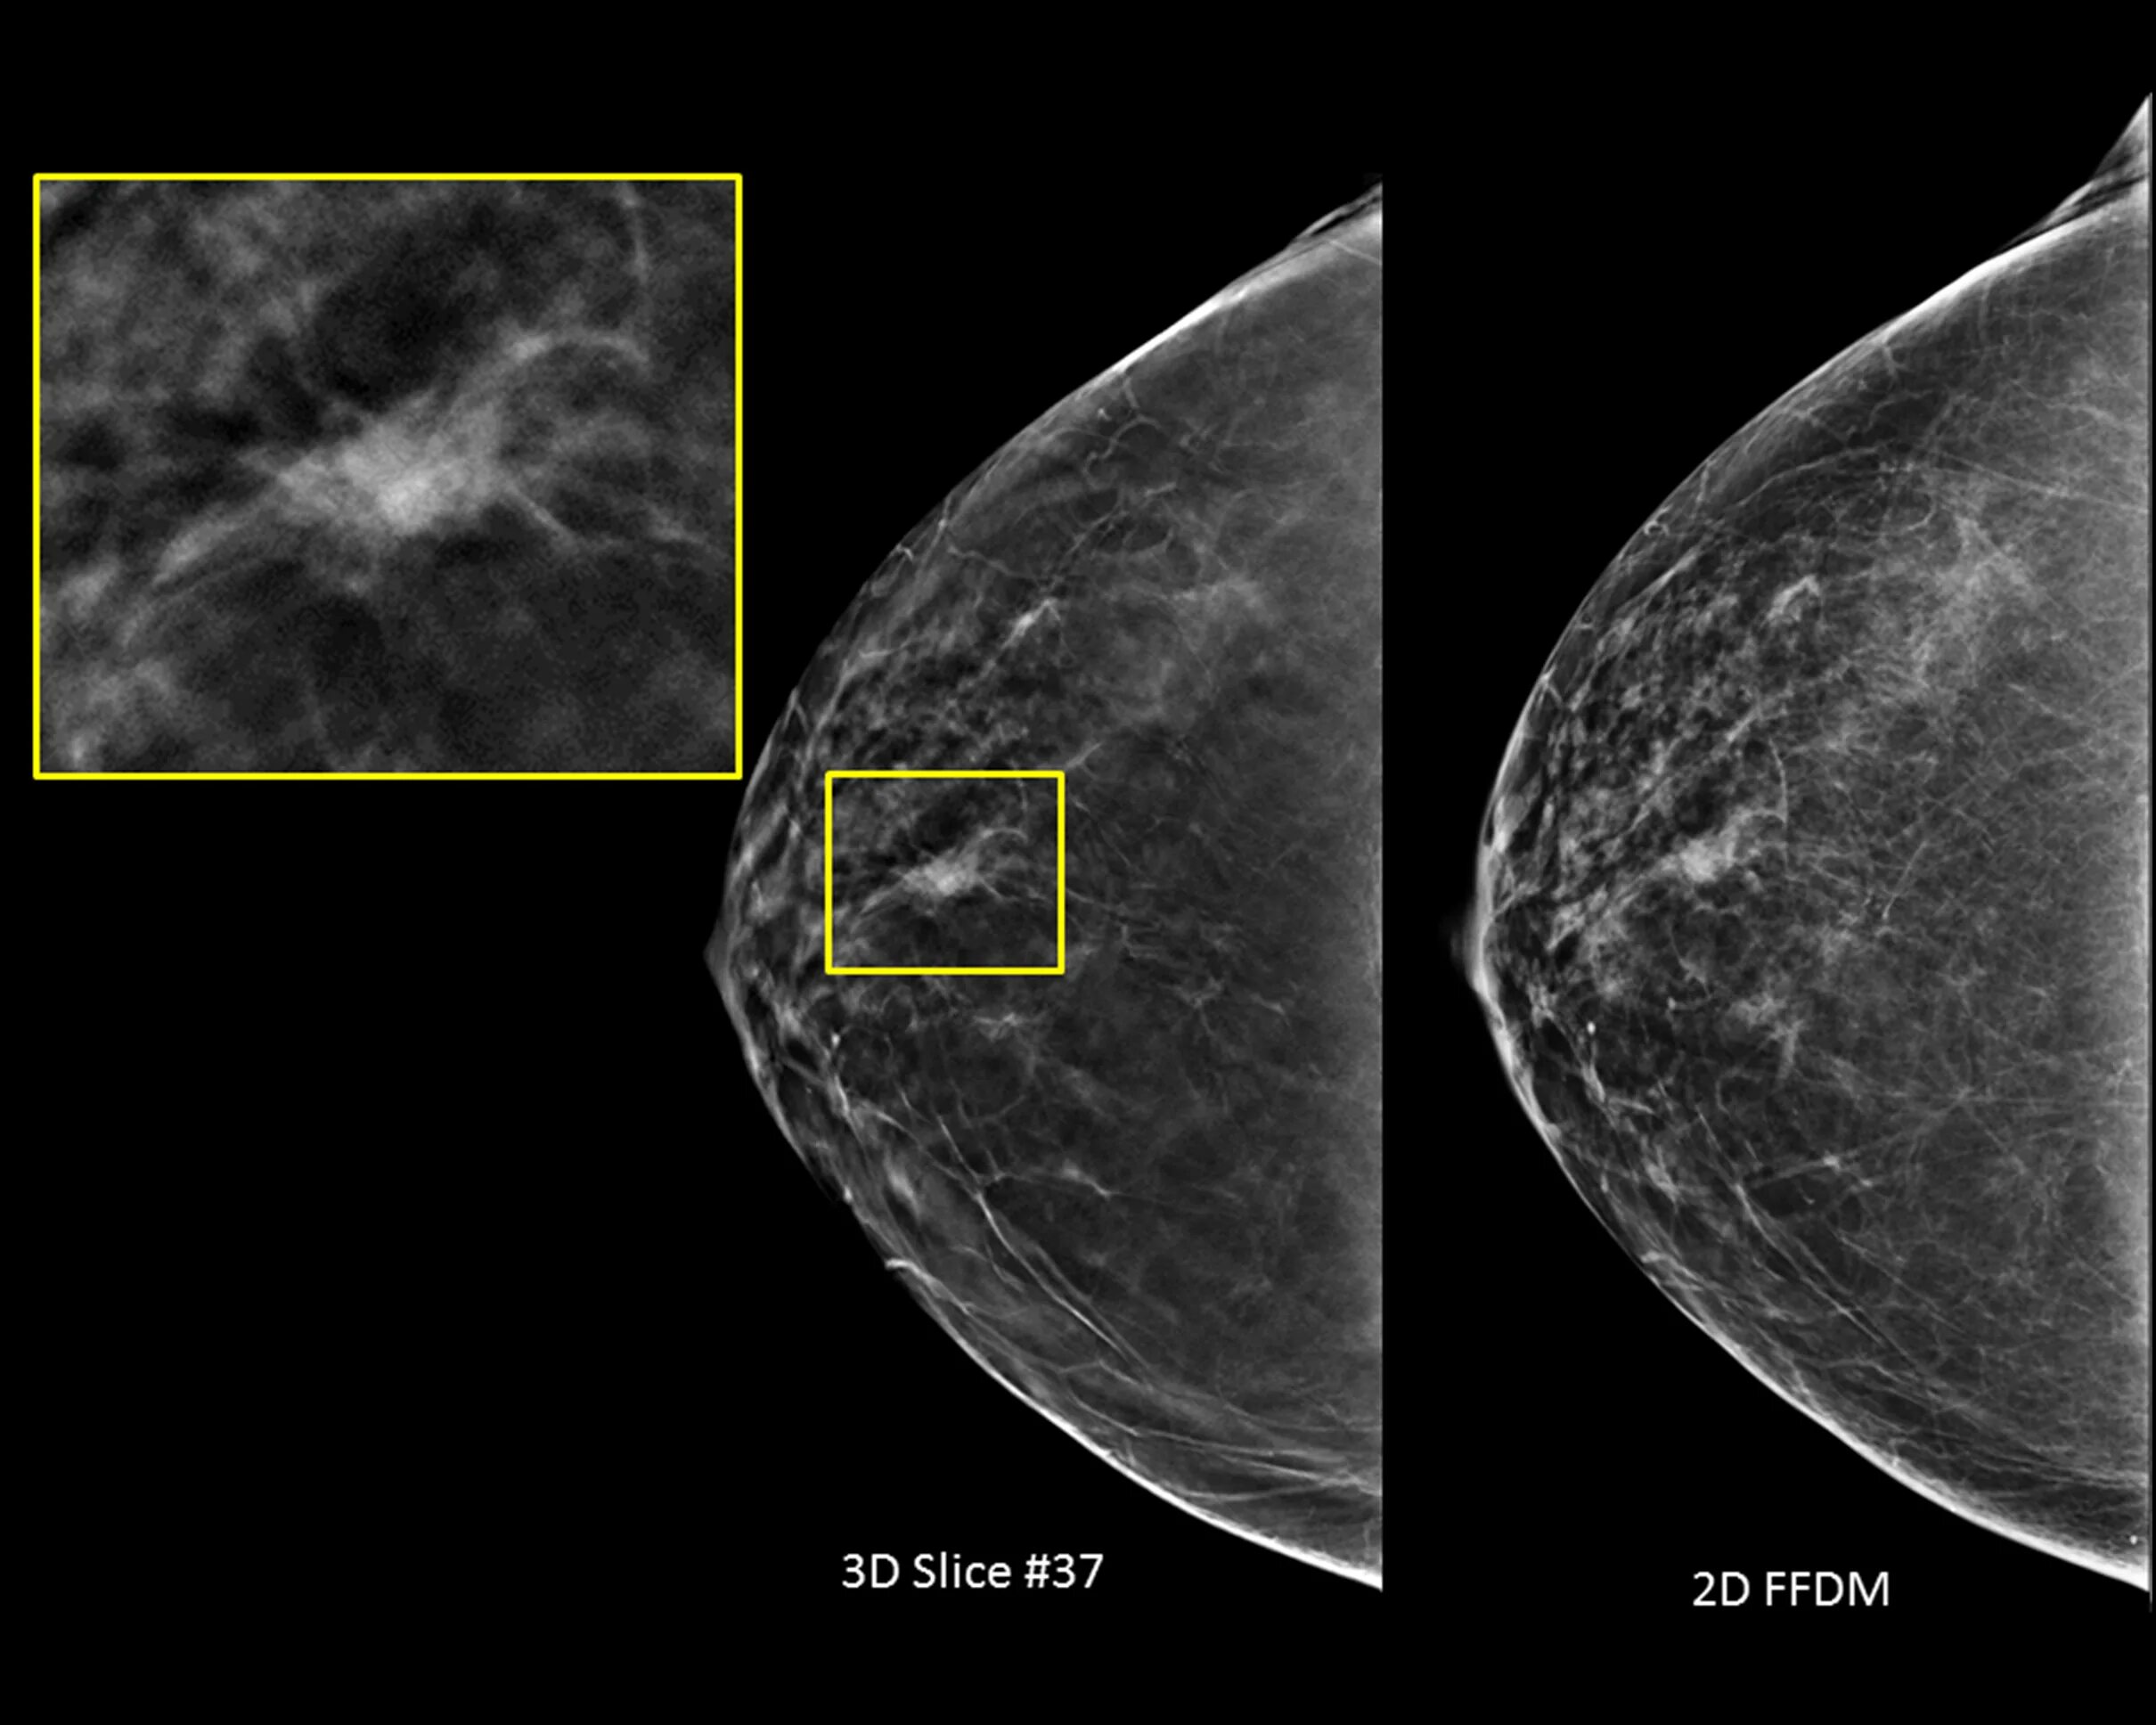

Тип строения молочных желез по acr